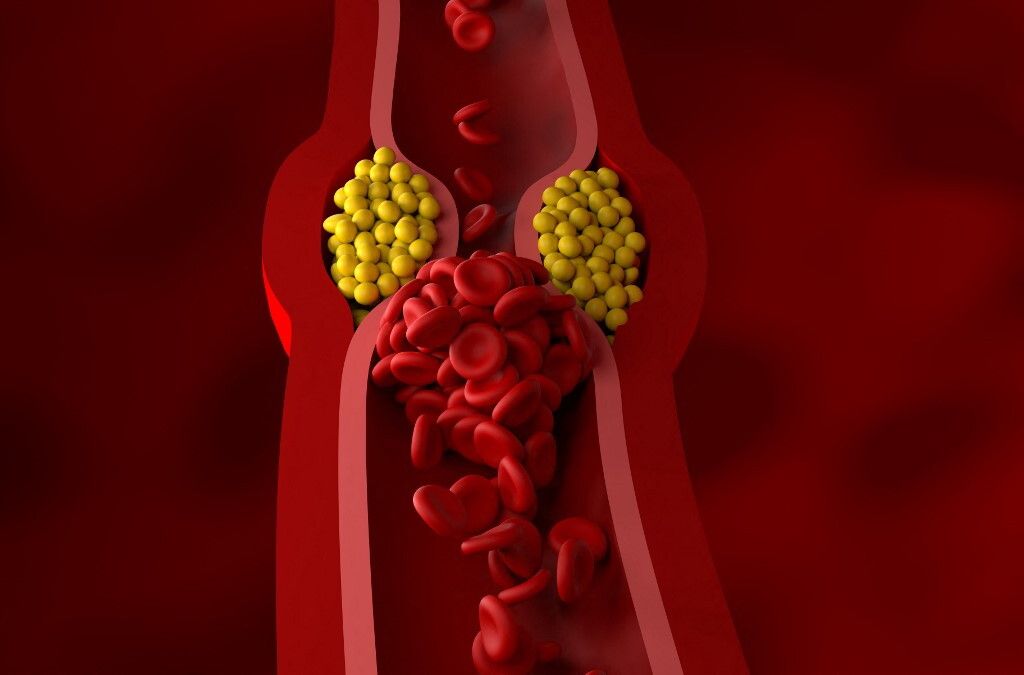

Oltre 100.000 persone negli Stati Uniti hanno attualmente bisogno di un trapianto di organi. La richiesta di organi, come cuori, reni e fegati, supera di gran lunga la reale disponibilità e le persone a volte aspettano anni prima di ricevere un organo. Ogni anno circa 6.000 americani muoiono per le lunghe tempistiche di attesa. L'ingegneria dei tessuti per creare organi e tessuti coltivati in laboratorio mira a colmare il divario tra la disponibilità di organi e la richiesta di trapianti. Ma, una grande sfida nell'ingegneria dei tessuti è la creazione di reti di vasi sanguigni negli organi artificiali, che funzionino come quelli naturali, dai piccoli capillari alle arterie più grandi.

I vasi sanguigni artificiali tradizionali spesso non imitano il disegno naturale necessario per riprodurre il normale funzionamento nell'organismo. Tuttavia, la nuova ricerca mostra la possibilità di utilizzare la stampa 3D del ghiaccio per creare strutture che assomigliano ai vasi sanguigni del corpo. La stampa 3D del ghiaccio prevede generalmente l'aggiunta di un flusso d'acqua a una superficie molto fredda. "Ciò che rende il nostro metodo diverso da altri tipi di stampa 3D è lasciare che l'acqua si congeli completamente durante la stampa, così che mantenga una fase liquida in cima", ha detto Yang. "Questo processo continuo, che chiamiamo 'freeform', ci aiuta a ottenere una struttura molto liscia", ha continuato Yang. "Non abbiamo l'effetto di stratificazione tipico di molte stampe 3D", ha spiegato Yang. Gli scienziati hanno anche utilizzato l'acqua pesante, una forma di acqua in cui gli atomi di idrogeno sono sostituiti dal deuterio, che conferisce all'acqua un punto di congelamento più elevato e contribuisce a creare la struttura liscia.

Queste sagome di ghiaccio stampate in 3D vengono poi incorporate in un materiale gelatinoso, il GelMA. Quando viene esposta alla luce UV, la gelatina si indurisce e il ghiaccio si scioglie, lasciando dietro di sé canali realistici per i vasi sanguigni. I ricercatori hanno dimostrato di poter introdurre cellule endoteliali, come quelle dei vasi sanguigni, nei vasi sanguigni artificiali. Le cellule sono sopravvissute sulla gelatina fino a due settimane. In futuro, i ricercatori intendono coltivare queste cellule per un periodo più lungo. Oltre al potenziale utilizzo per il trapianto di organi, Yang sottolinea che i vasi sanguigni stampati in 3D potrebbero essere utilizzati per testare gli effetti dei farmaci sui vasi sanguigni. Potrebbero anche essere rivestiti con le cellule di un paziente per vedere come le cellule rispondono a un trattamento farmacologico prima di somministrarlo al paziente. "Questo approccio innovativo potrebbe rappresentare un significativo passo avanti nella creazione di reti di vasi sanguigni complessi e realistici da utilizzare nell'ingegneria dei tessuti", ha concluso Yang.